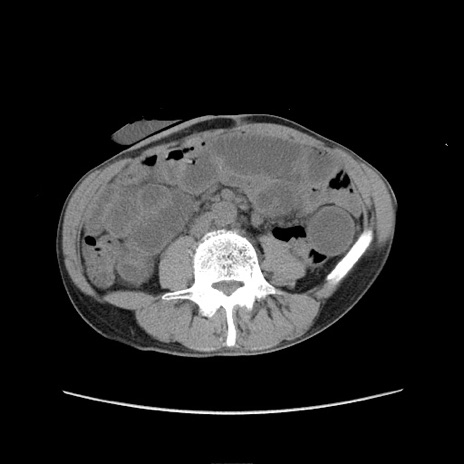

症例11(横断像)

【症例】 60歳代男性

【主訴】 下腹部痛

【現病歴】 本日夜中より下腹部痛の症状認め、受診。

【既往歴】 膀胱癌(膀胱全摘+尿管皮膚瘻術) 、胃癌術後

【身体所見】 BT 35.3℃、PR 58/min、BP 136/98mHg、腹部平坦、軟、腸蠕動音±、ストマ留置あり、左上腹部~正中部に圧痛あり、反跳痛なし。

【データ】WBC 5100、CRP0.01